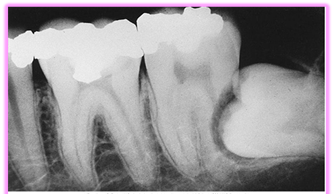

Då visdomständerna är de sista tänderna i bettet att eruptera är förekomsten av total eller partiell retention av visdomständer relativt vanligt. 72% av svenskarna i åldrarna 20 till 30 år har minst en retinerad visdomstand. De kan orsaka smärta, svullnad och infektion – och kan förstöra angränsande tänder och ben. Operativt avlägsnande av visdomständer är ett av de vanligaste kirurgiska ingreppen inom tandvården. Preoperativ bedömning av kirurgiska svårigheter är grundläggande för planeringen inför operativt avlägsnande av retinerade visdomständer. Vinsten av operationen ska alltid överstiga risken med ingreppet. Bedömningen är inte bara viktig för beslut om patienten ska remitteras till specialist eller inte, utan också för att informera patienten om eventuella risker och komplikationer i samband med det operativa ingreppet.

- Karies

- Parodontal sjukdom med ficka > 5 mm distalt på 7:an

- Kron/rotresorption